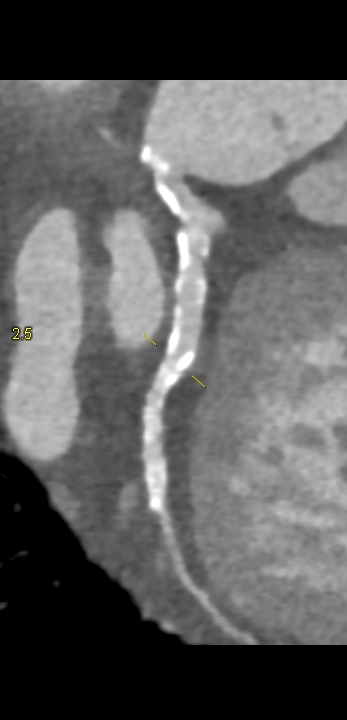

Figura 4: reconstrucție “în lungul vasului” artera coronară dreaptă din achiziția angiocoroCT